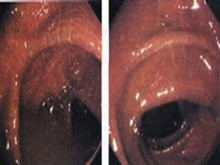

结直肠黑变病是指结直肠固有膜内巨噬细胞含有脂褐素样物质的粘膜色素沉着性病变。国内...